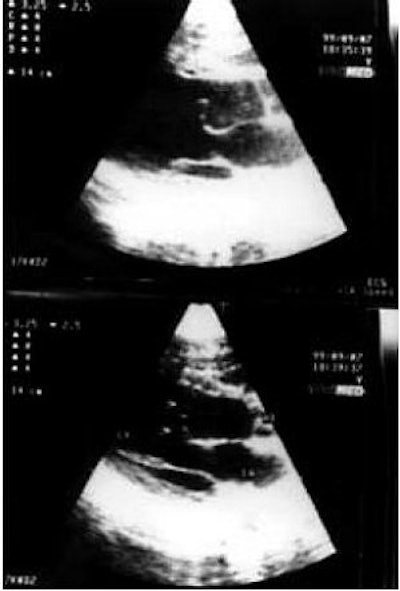

![]() |

| Patients with HCM have a characteristic thickening of the heart walls that can range from 14-60 mm. Particular thickening of one part of the heart, the interventricular septum, is characteristic of patients with HCM. The thick interventricular septum is marked with an asterisk. Images courtesy of the Hypertrophic Cardiomyopathy Program, St. Luke's-Roosevelt Hospital Center, New York City. |